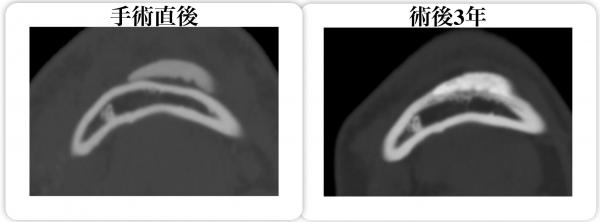

また、CT-Boneは他の人工骨のように焼結しないため、生理的に活性化された人工骨となり、母骨への癒合が早く、時間の経過につれて患者自身の骨へ同化するのが特長です。

引用文献:Yuki Kanno et al. Computed tomographic evaluation of novel custom-made artificial bones, “CT-bone”, applied for maxillofacial reconstruction.Regenerative therapy 5(2016)1-8